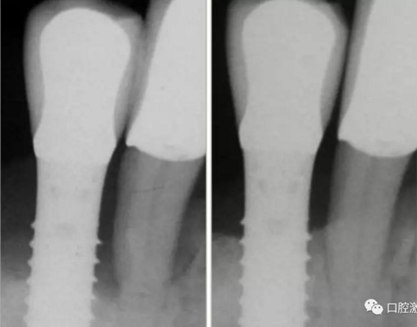

激光非手術(shù)種周炎治療前與治療后2年的對比